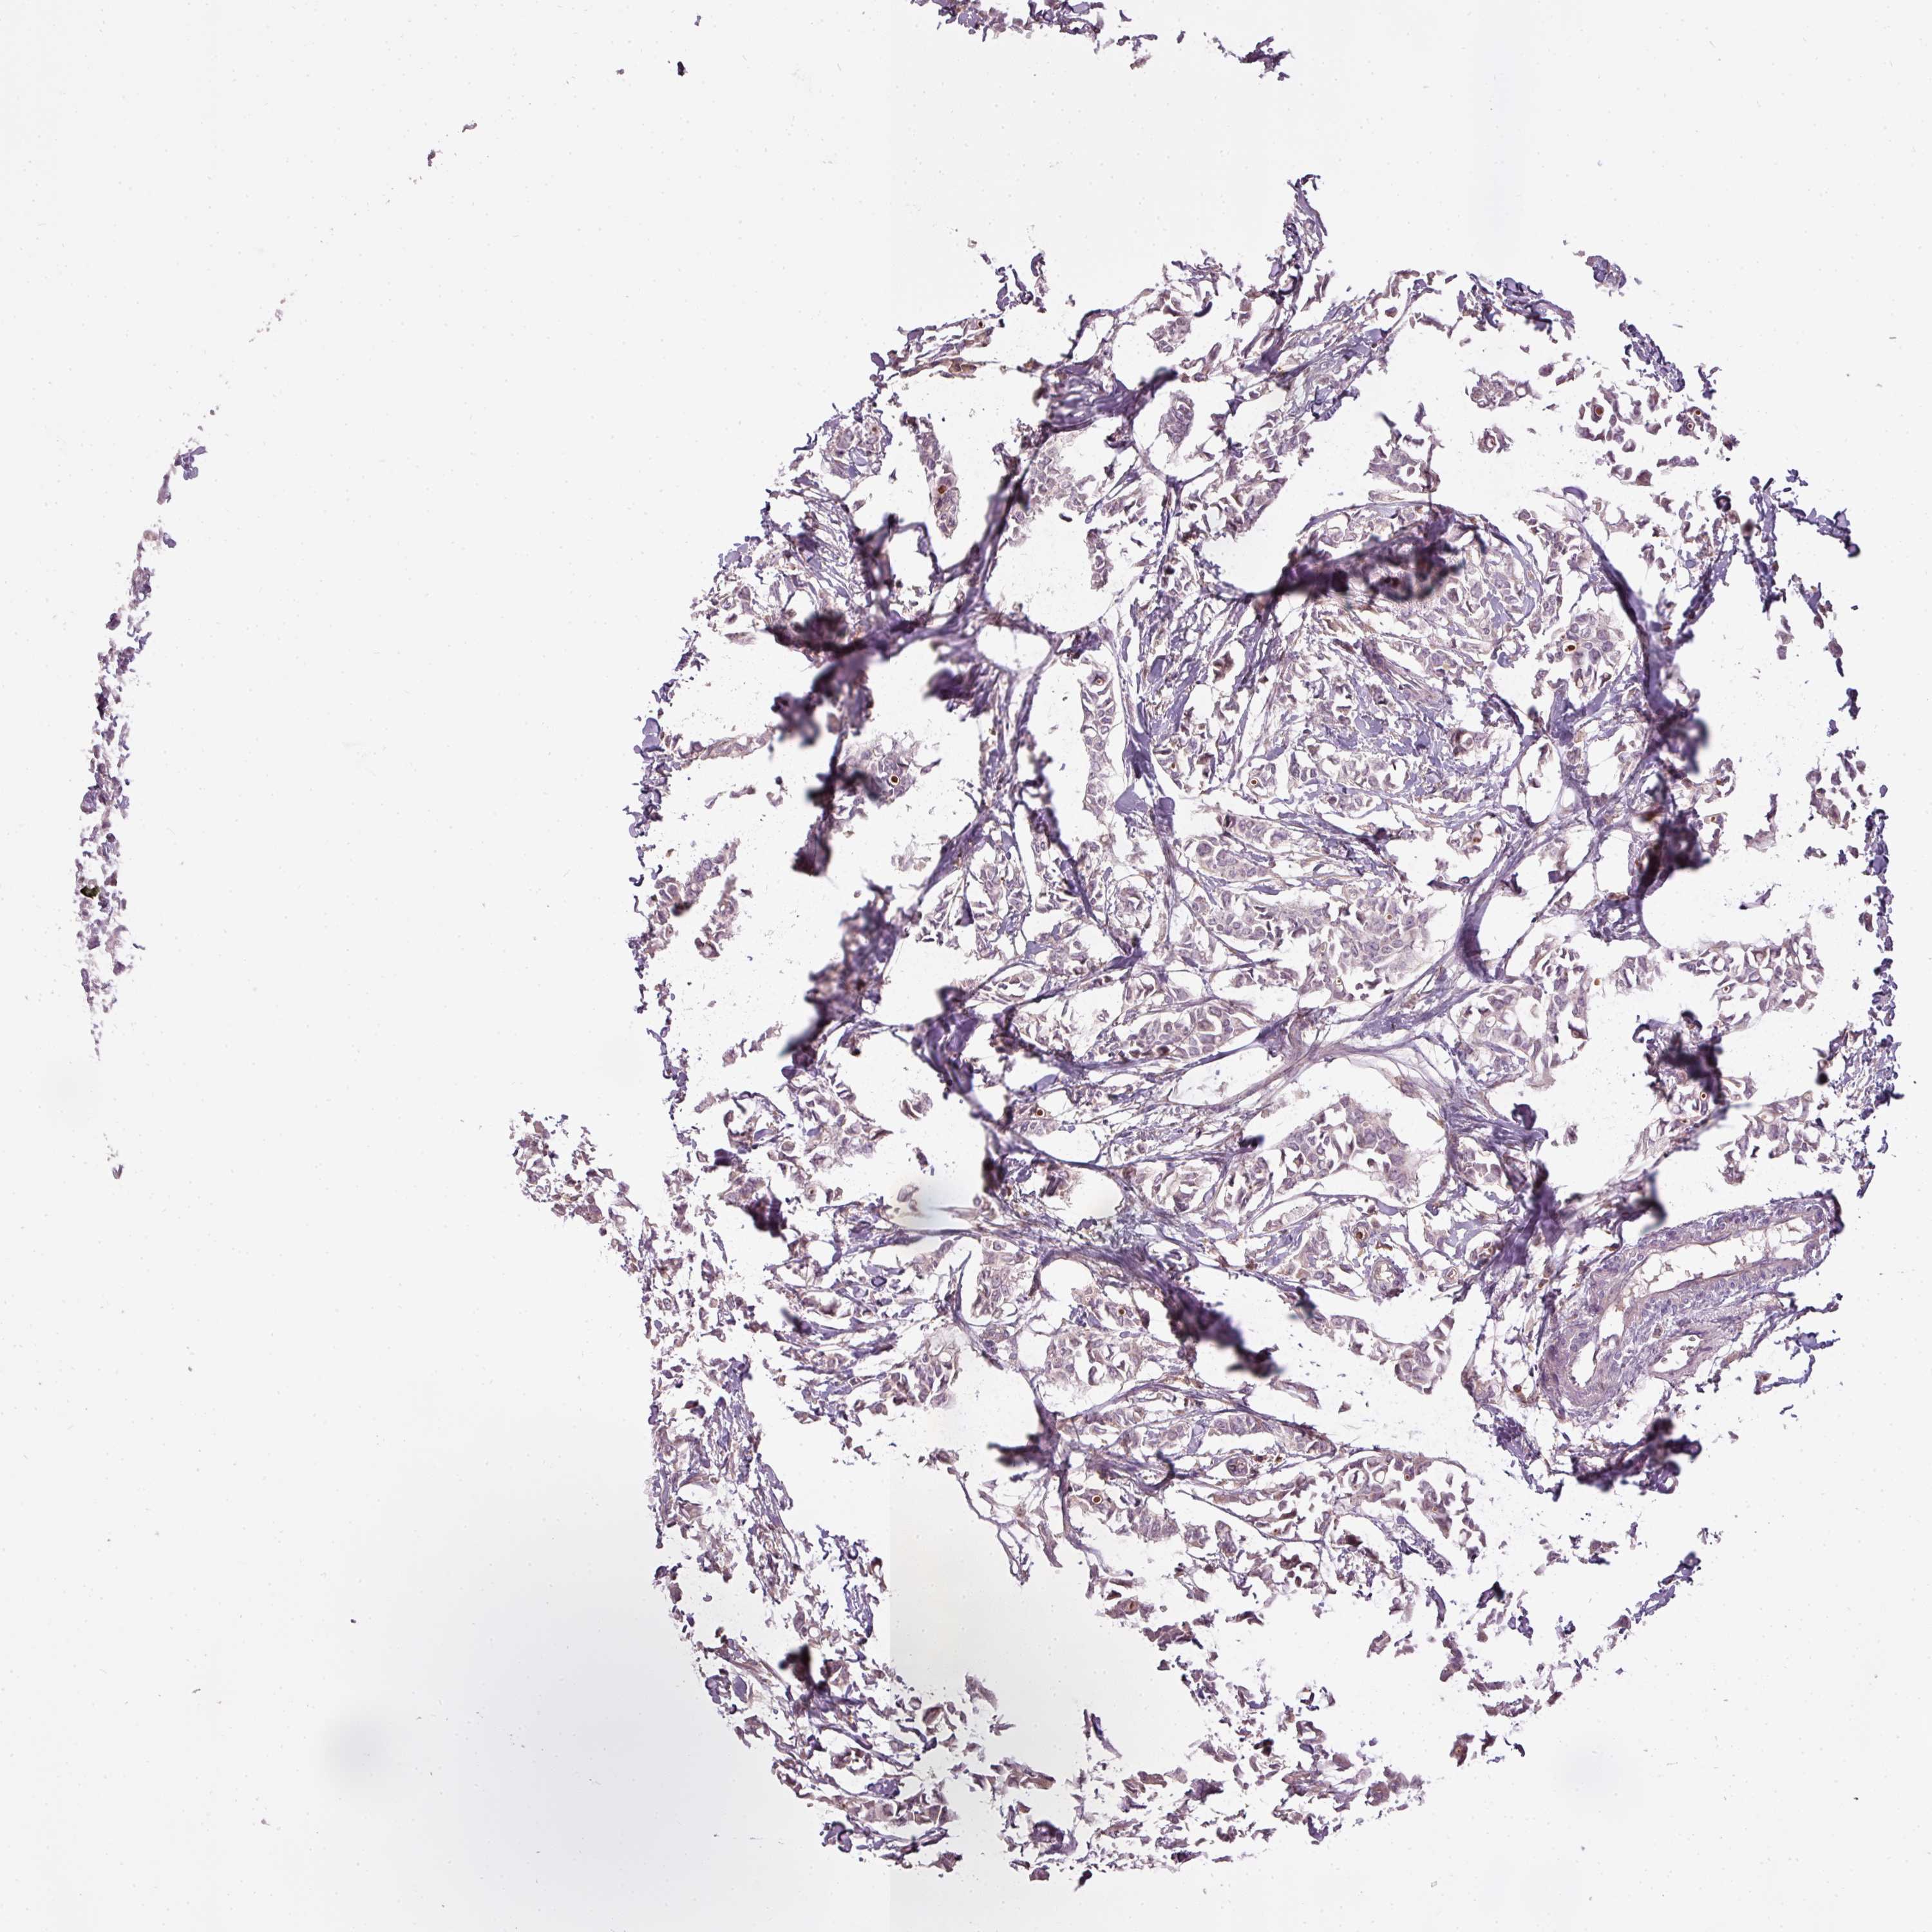

BRCA TCGA BRCA VALIDATION PROTEIN EXPRESSION